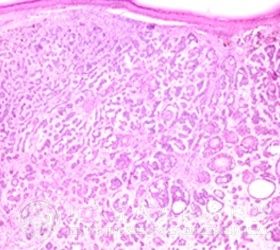

基底*癌是一种恶性肿瘤,一般中老年患者较多,多发生于头面部等曝光部位,尤以鼻、眼睑及颊部较为常见。

基底*癌表面形成多种多样,大致可分为以下几种类型: